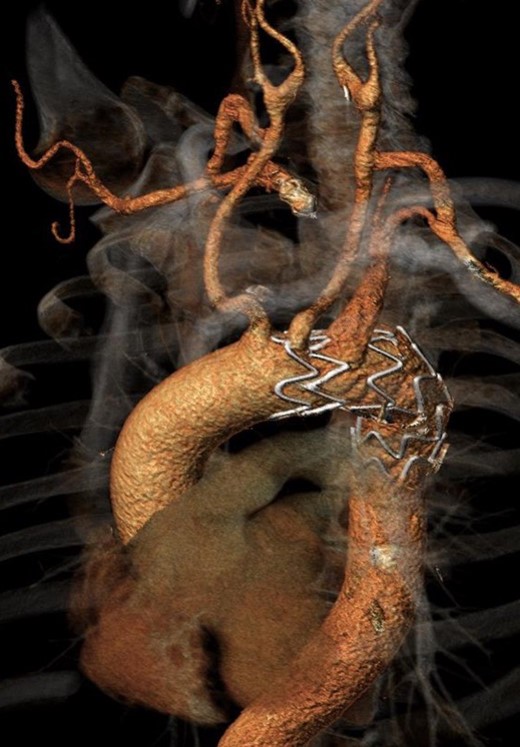

A male patient, aged 73, with a history of hypertension and Pott Disease, was referred to our Unit for dysphagia and incoercible cough. The diagnostic angio-computed tomography (CT) scan showed a retroesophagel AARSA with a maximum diameter of 70 mm, determining the compression of both esophagus and trachea, with a dominant left vertebral artery (Fig. 1). Both aortic arch and thoracic aorta were not involved in the aneurysmal degeneration and no significant intra- and extracranic carotid stenoses were described. A hybrid surgical approach with was planned to exclude the AARSA and to preserve the inflow of both subclavian arteries. It consisted of a bilateral common carotid-to-subclavian artery bypass with a 7 mm expanded polytetrafluorethilene (ePTFE) prosthetic graft and the deployment of thoracic endoprosthesis (Cook Medical Inc, Bloomington, IL ZTA-P-40-117) distally to the left carotid ostium to exclude the aneurysm. The distal neck of AARSA was embolized with a 16 mm Amplatzer vascular plug. Complete technical success without evidence of endoleak was detected at the end of procedure. The embolization of the left subclavian artery at its origin was not performed because the stent-graft completely covered its ostium and it was well adherent to it. The postoperative medical therapy consisted of subcutaneous sodium enoxaparin for the first postoperative month and single antiplatelet treatment indefinitely. The patient was discharged on the ninth postoperative day and underwent angio-CT scan at 1 month (Fig. 2) and yearly thereafter. The 1-year angio-CT scan showed the development of a Type II endoleak from bronchial arteries without significant sac enlargement.